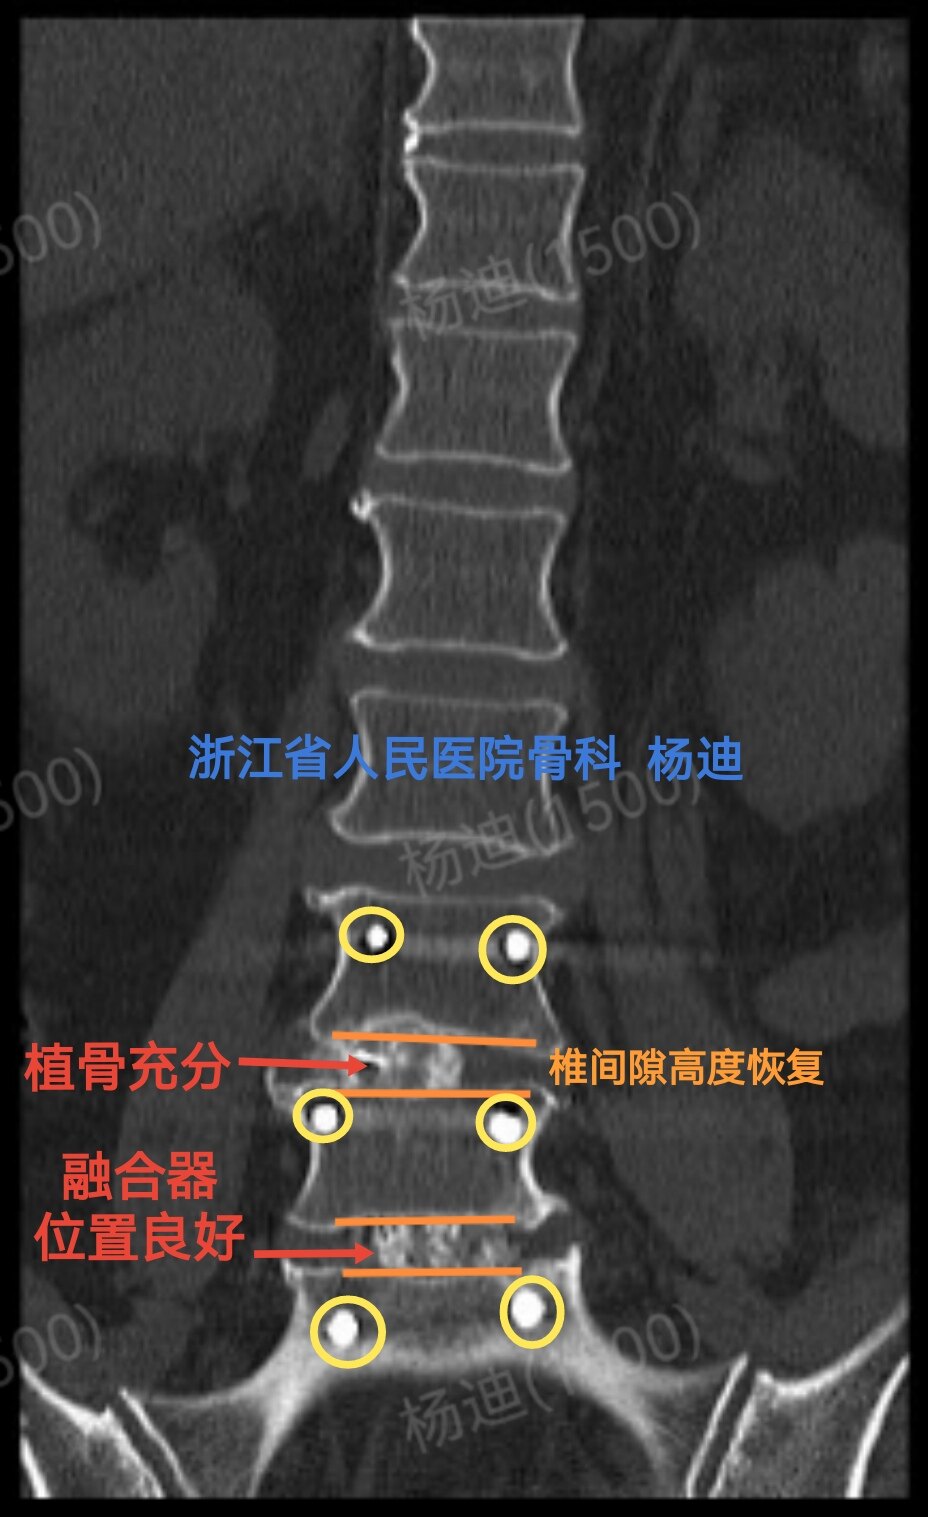

图为术后腰椎CT矢状位重建:椎间隙高度恢复(橙色直线间距离),融合器位置良好,植骨充分(红色箭头)。

图为术后腰椎CT矢状位重建:椎间隙高度恢复(橙色直线间距离),融合器位置良好,植骨充分(红色箭头)。

CT冠状位重建:椎间高度恢复(橙直线间距离),融合器位置良好植骨充分(红箭头),螺钉位置良好(黄圈)